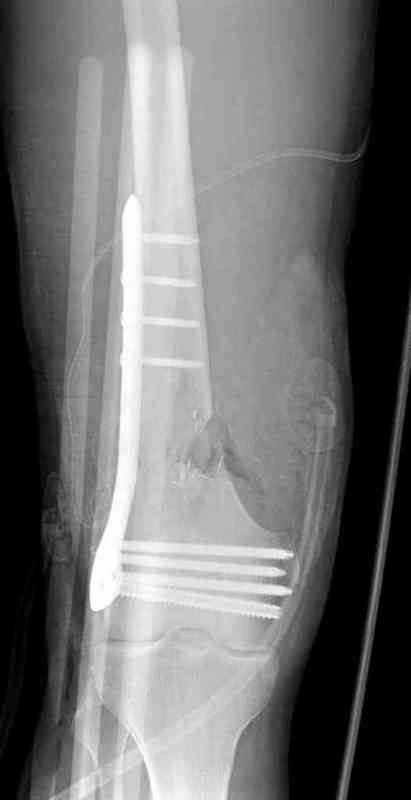

Огнестрельный перелом бедра

Вдогонку к обсуждению случая несращения дистального отдела бедра 9 мая утром поступил больной с огнестрельной раной, осмотрен сосудистым специалистом, сделана ангиограмма (снимки)

Во время операции при вскрытии обнаружили кровотечение, рану забили салфетками, установили пластину locking DePuy.

Из-за возрастающего давления в компартменте сделана фасциотомия и вызванный сосудистый хирург ушил разрыв вены на уровне перелома. Все раны оставлены открытими, в пятницу закроем.